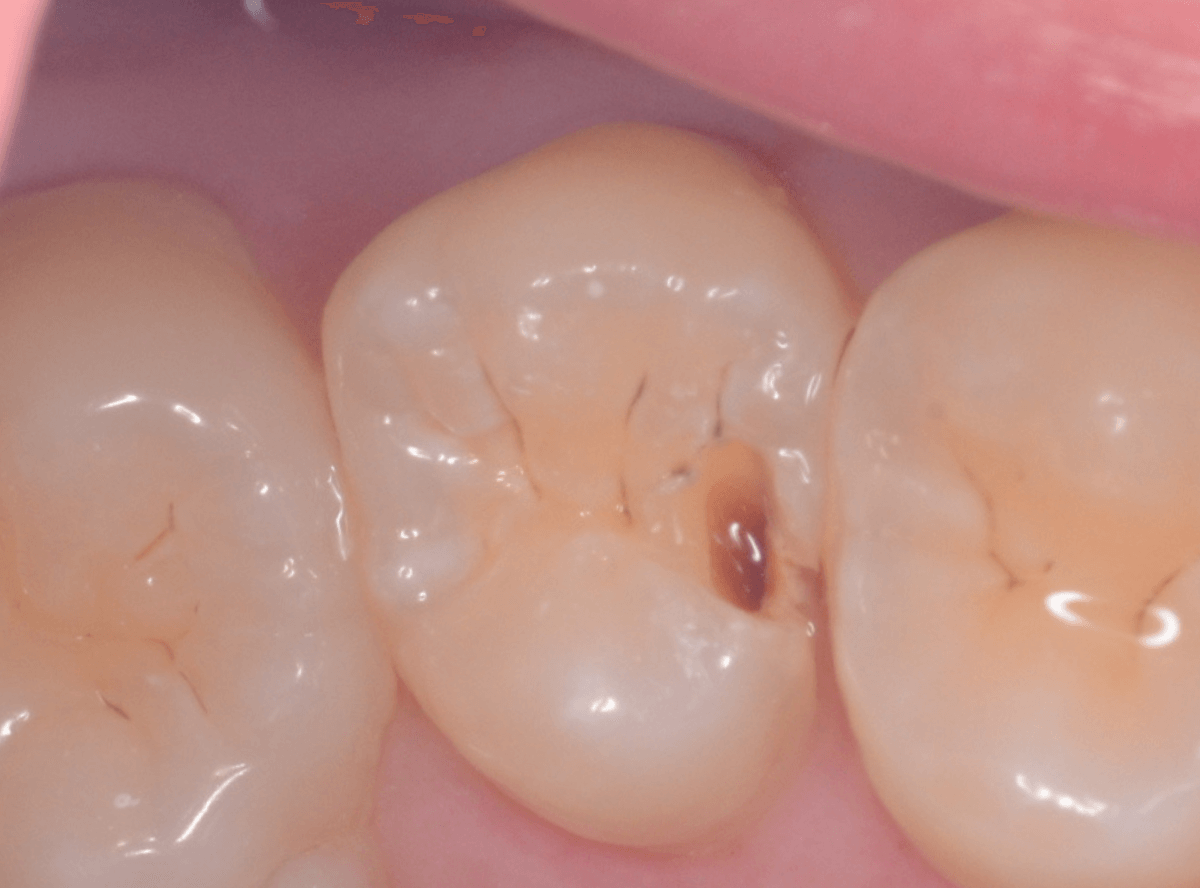

こちらも定期検診希望で来院された患者さんです。

お口の中を拝見すると、明らかに虫歯がありました。

3本虫歯になっており、特に中央の小臼歯はかなり大きな虫歯になっているのが予想されます。

治療前にレントゲン写真で虫歯の大きさを確認するつもりが・・・あまりはっきり写ってきません。

患者さんに状況を説明して、歯を少しずつ削りながら虫歯を確認する事になりました。

まず、一番大きな虫歯と思われる部分を小さく削って確認します。

予想通り、虫歯が見えてきました。

特に手前の歯はかなり広めの虫歯になっていました。

このように明らかに大きな虫歯があると診断されるような状況でも、レントゲン写真でうまく診断できない場合もあります。